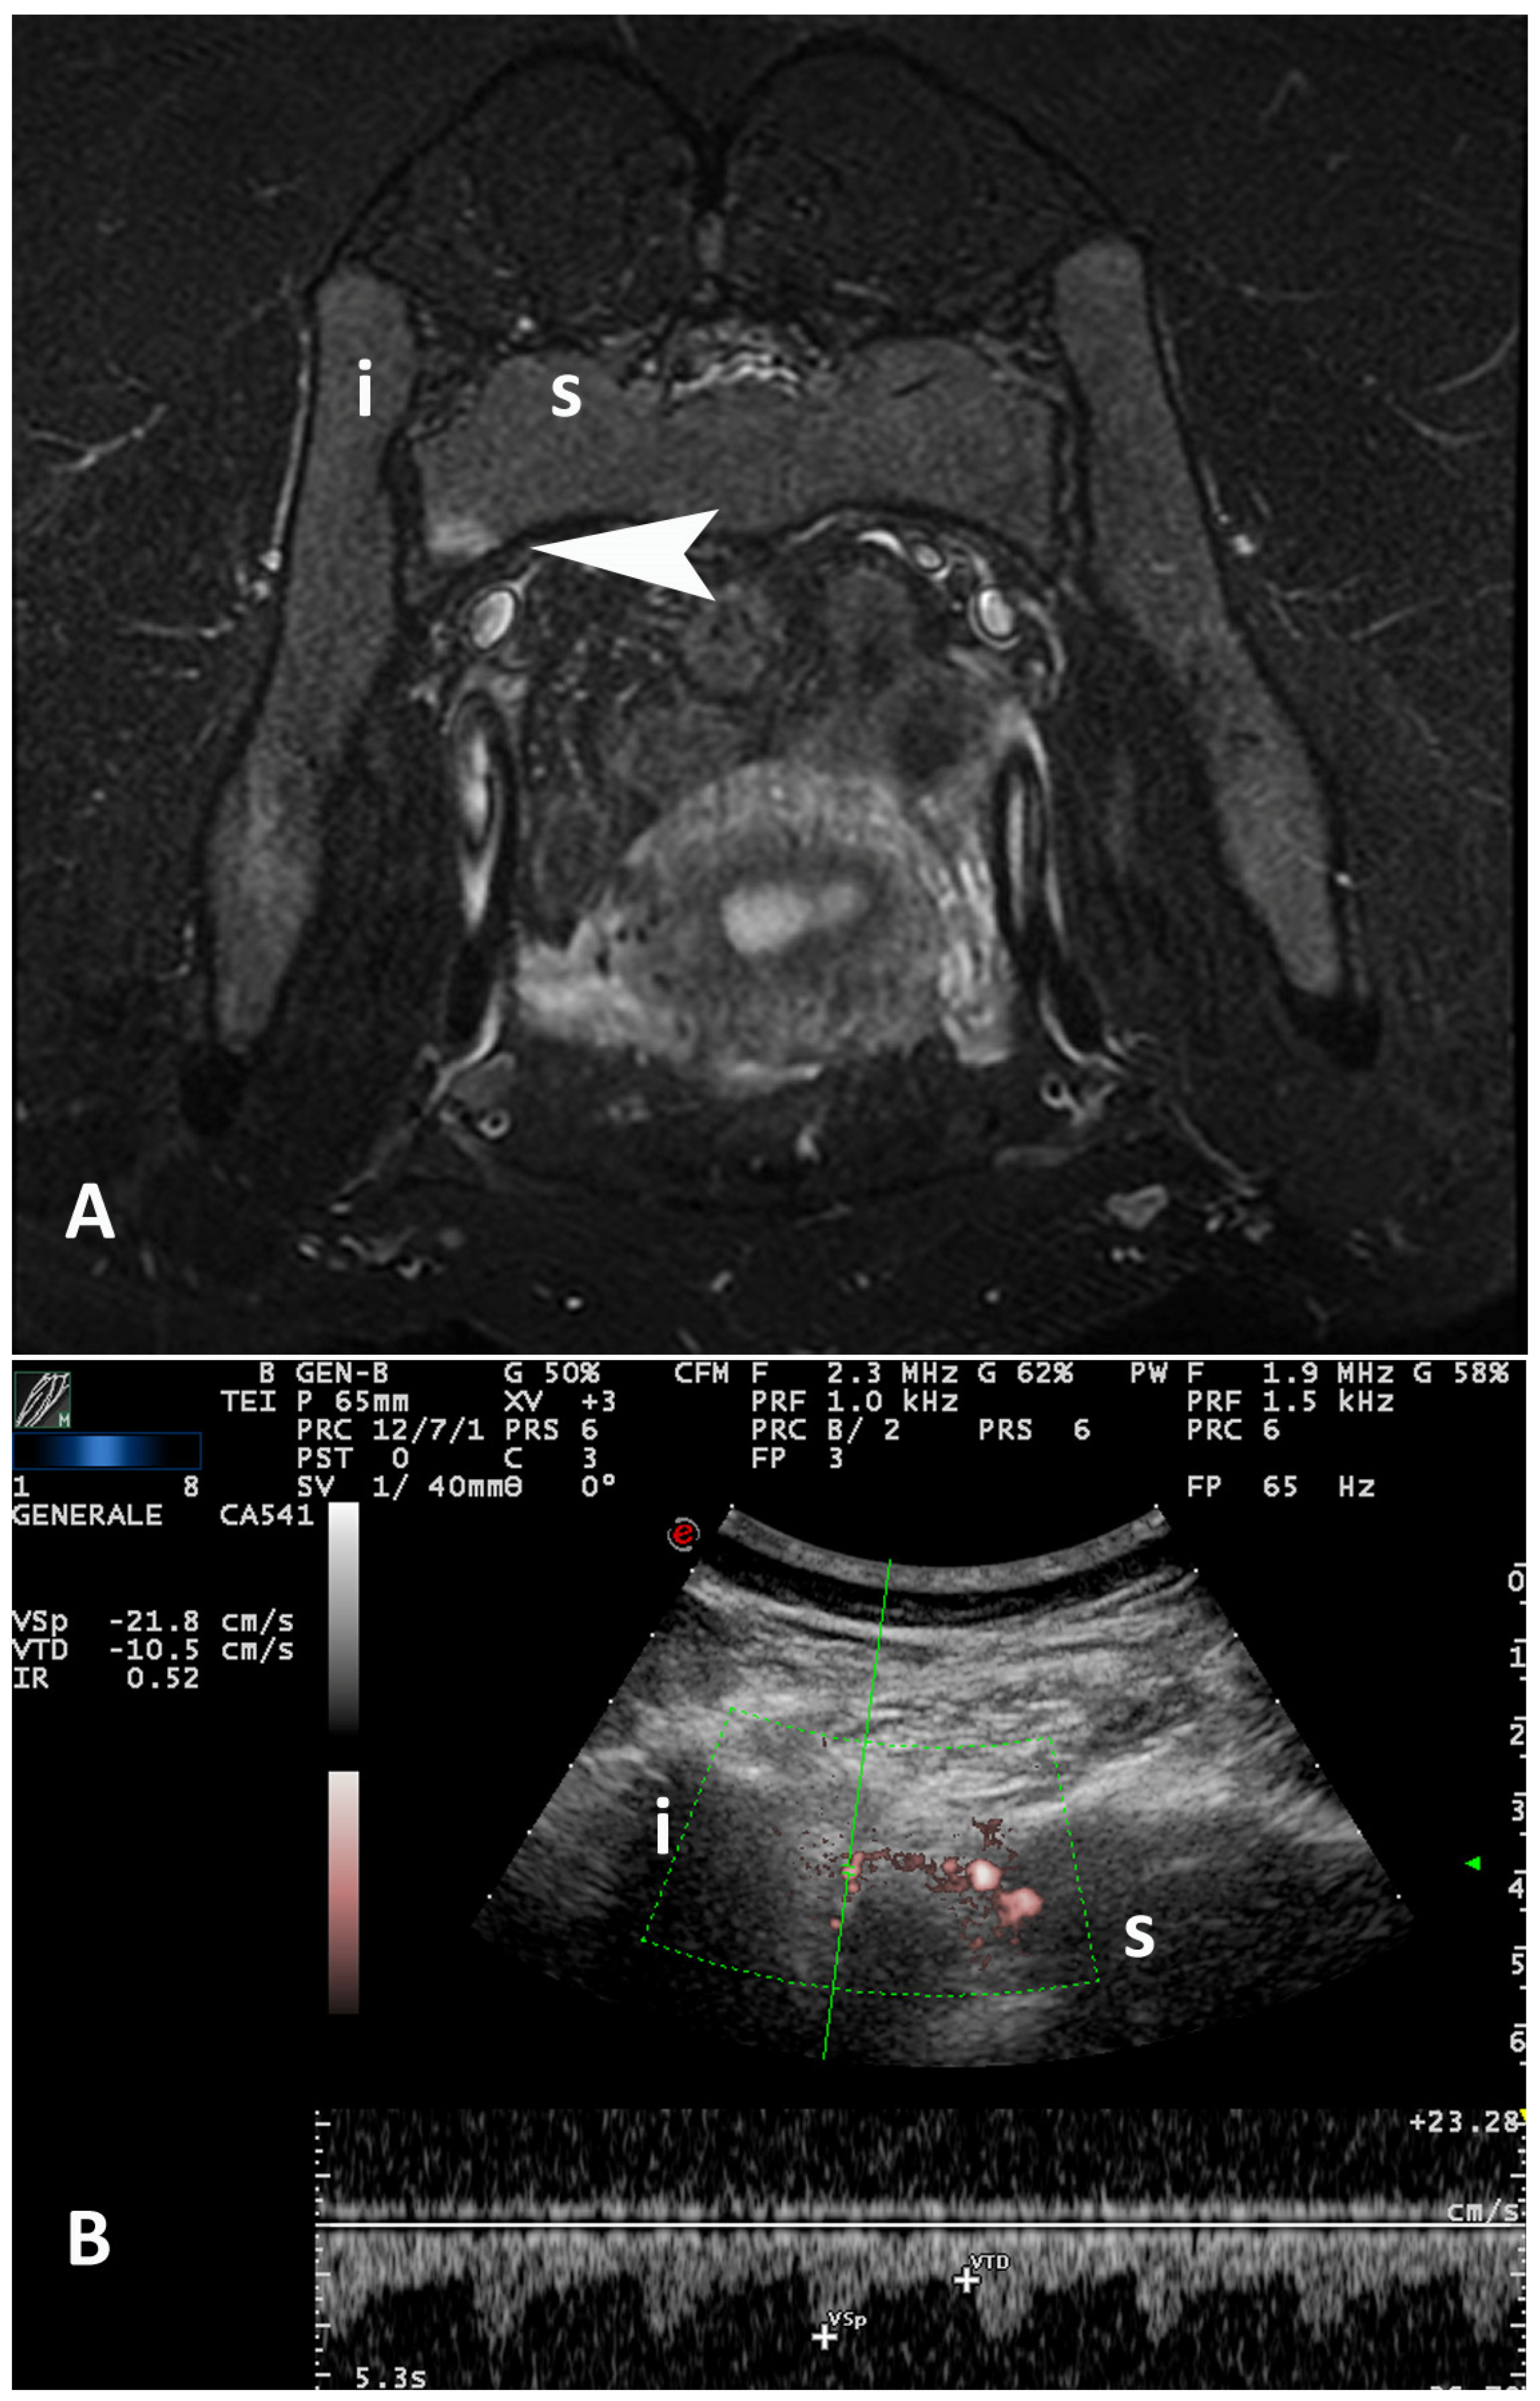

| -Patients with PDUS+ -SIJs with PDUS+ | 19 patients (95%) 30 SIJs (75%) | 12 patients (100%) 21 SIJs (87.5%) | 7 patients (87.5%) 9 SIJs (56.2%) | n.s. n.s. |

| SIJs PD grading (±SD) patient level | 1.20 (±0.523) | 1.42 (±0.515) | 0.875 (±0.354) | p = 0.012 * |

| SIJs PD grading (±SD) joint level | 0.912 (±0.668) | 1.13 (±0.612) | 0.563 (±0.512) | p = 0.003 ** |

| SIJs RI (±SD) patient level | 0.583 (±0.115) | 0.534 (±0.092) | 0.656 (±0.112) | p = 0.024 * |

| SIJs RI (±SD) joint level | 0.671 (±0.181) | 0.604 (±0.155) | 0.767 (±0.176) | p = 0.005 ** |